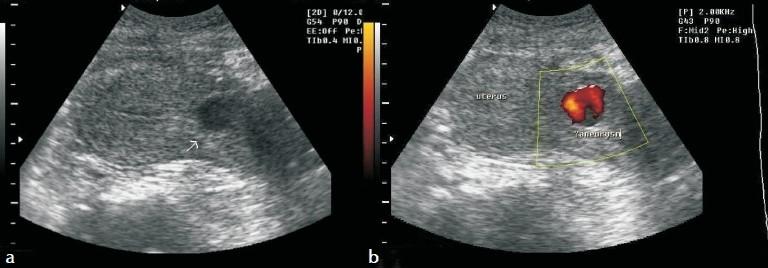

Uterine artery pseudoaneurysm is a rare cause of secondary postpartum hemorrhage but is potentially life-threatening and can occur after caesarean section (c-section) or a hysterectomy. A 28-year-old woman who developed secondary postpartum hemorrhage after c-section was diagnosed to have pseudoaneurysm from the left uterine artery on ultrasound (US) and computed tomography (CT) scan. She was treated with coiling of the pseudoaneurysm with stainless steel coil via selective catheterization of the uterine artery. The procedure was uneventful and the pseudoaneurysm was successfully obliterated. Angiographic embolization is a safe and effective method for treating postpartum hemorrhage due to pseudoaneurysm in hemodynamically stable patients. Therefore, it should be considered as a treatment option before resorting to surgery, in appropriately selected cases.

子宫动脉假性动脉瘤是继发性产后出血的罕见原因,但有潜在生命危险,可发生于剖宫产或子宫切除术后。一名28岁女性在剖宫产后发生继发性产后出血,经超声(US)和计算机断层扫描(CT)诊断为左子宫动脉假性动脉瘤。通过子宫动脉选择性插管,用不锈钢线圈对假性动脉瘤进行了栓塞治疗。手术过程顺利,假性动脉瘤成功闭塞。对于血流动力学稳定的患者,血管造影栓塞术是治疗假性动脉瘤所致产后出血的一种安全有效的方法。因此,在适当选择的病例中,在采取手术治疗之前应考虑将其作为一种治疗选择。